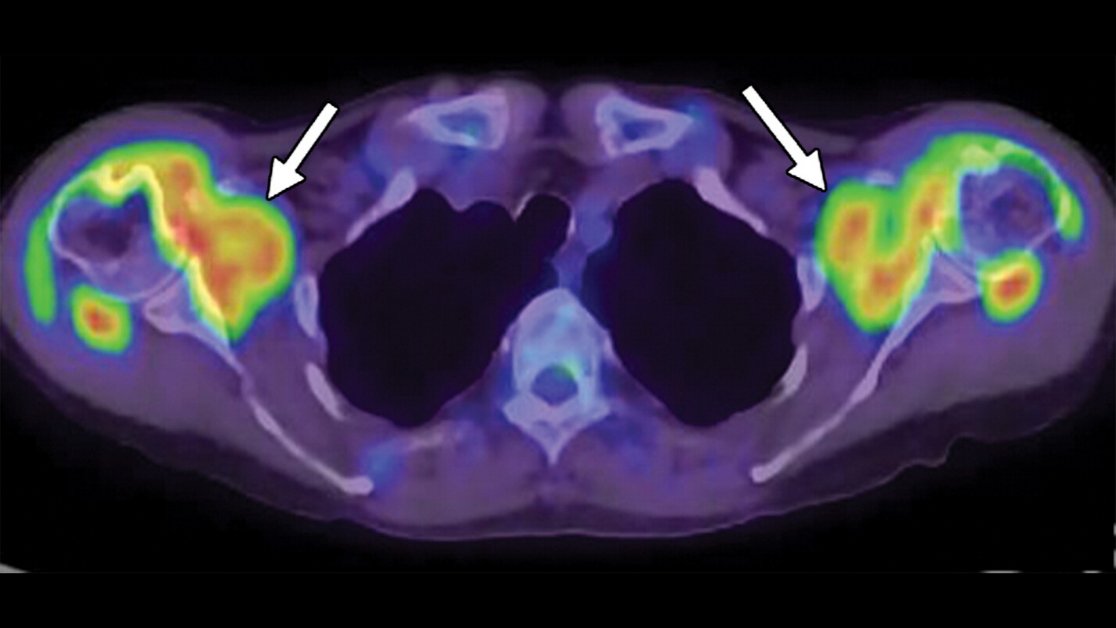

Differentiate rheumatic diseases (

#rheumatoidarthritis and allied disorders, spondyloarthritis, miscellaneous systemic disorders with arthropathy) using FDG PET/CT, accurately demonstrates inflammatory lesions of arthritis. https://bit.ly/35JEohq@MasatoshiHotta#RadCME#NucMedpic.twitter.com/sUXlVyD0hI